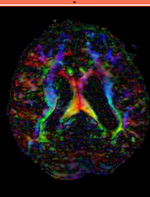

Registration Results (click to enlarge)

RegLib C03 DTI registered.gif

baseline & T2 before registration baseline to T2 after affine+nonrigid alignment DTI and T2 before & after registration